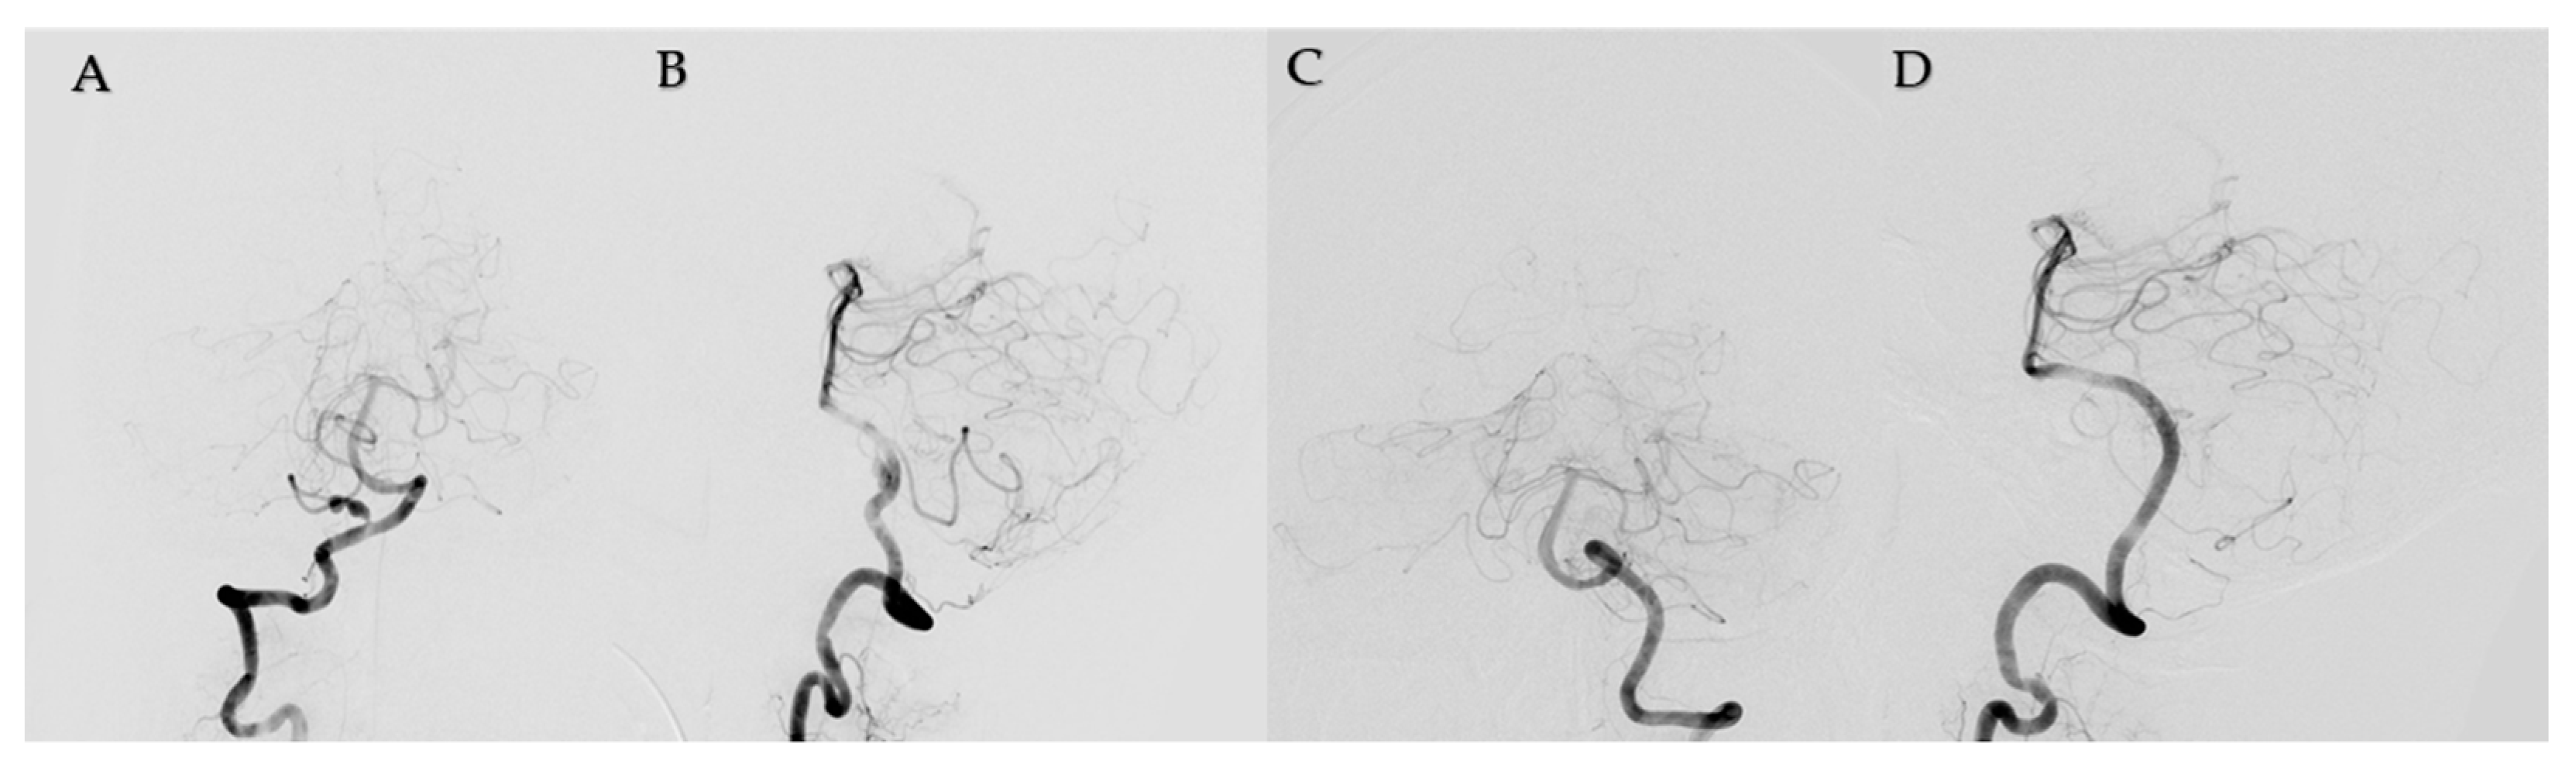

2. Case Report